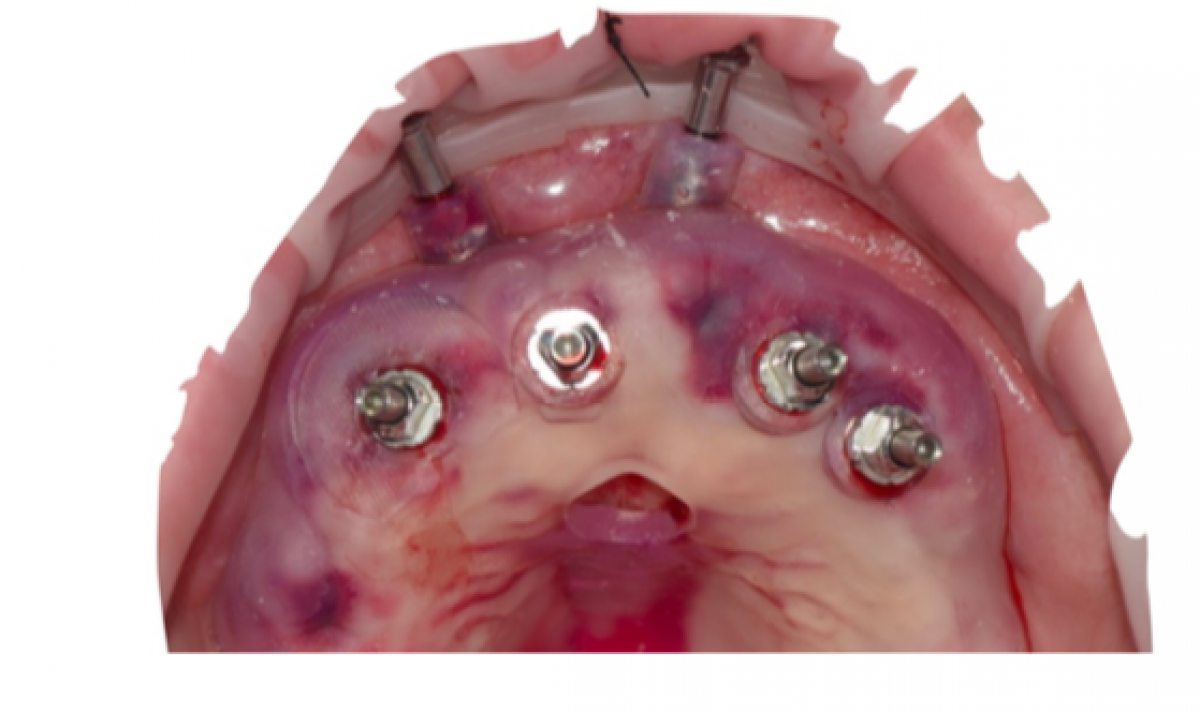

Once inserted all the implants with the corresponding mounter and once reached the minimum torque demanded for the immediate load, the splint is removed.

For the insertion of zygomatic implants, a minimal invasive access is obtained with an incision of 5 mm in the palatal crest and vestibular discharges in 1.4-1.7 and 2.4-2.7 areas.

A skeletonization of the maxillary bone is performed, together with an exposure of the lateral wall of the maxillary sinus, the infraorbital nerve and the zygomatic pommel (till when the anterior mar- gin of the tendon of the maseteric muscle is exposed).

It is finally identified the ideal pathway of the two zygomatic implants, by detecting the position of the first molar tooth on both walls of the maxillary crest.

It is then performed, along the right implant pathway, an osteotomy of the lateral side of the maxil- lary sinus through a small silver sphere suitable to allow a moderate detachment of the Schneider membrane. A further osteotomy of the lateral wall is performed with a circular diamond coated drill; this final osteotomy defines the natural placement for the drill for the final osteotomy. FIG 7

Once defined the new alveolus, the zygomatic implant is inserted following the prosthetic project.

After a careful homeostatic control, it’s possible to proceed to the suturing of the mucosal folds.

All the inserted implants have now reached an insertional torque sufficient enough to perform an immediate loading. FIG 8